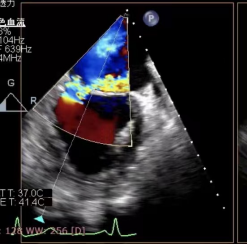

检查显示二尖瓣重度返流

被送到ac米兰官网中文网站二院急诊科后,孙先生的病情急转直下,急诊科立即组织抢救,同时边抢救边转入心内科重症监护室,监护室杨爽主任医师和刘芳副主任医师立即组织抢救、麻醉、气管插管、有创呼吸机支持,并给予药物维持生命体征,经过一番抢救后,患者情况暂时控制住了。另一边,心内科导管室手术陈涛副主任医师和杨光副主任医师,对患者病情进行评估并立即向于波汇报,在于波指导协调下,对患者进行了急诊冠脉造影排除冠脉疾病,同时在超声医学科副主任冷晓萍教授团队的配合下进行急诊食道超声,最终诊断患者是由于腱索断裂导致二尖瓣后叶脱垂造成二尖瓣重度返流,最终导致急性肺水肿,低血压休克。